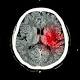

RAH stroke doctors doubled up on leave — again The Advertiser As SA Health investigates the deaths of two stroke patients when the Royal Adelaide Hospital’s only two specialists were simultaneously rostered on leave, it’s emerged that these two doctors were rostered for leave at the same time again. In the case … Stroke surgeons’ holidays prompt questions about staffing ... |